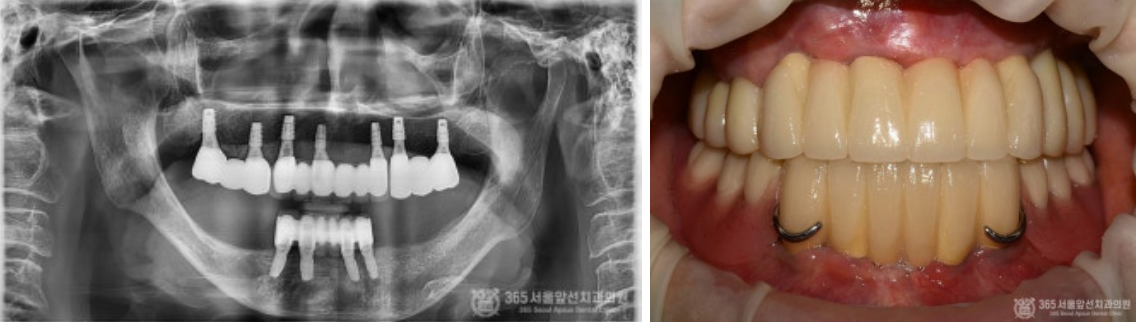

골다공증이 심해서 임플란트가 불가능하다는 이야기를 들었어요. 임플란트가 가능할까요? 상기 환자분은 골다공증으로 치료를 받고 계신 환자분이십니다. 골다공증제를 복용하고 계시거나, 골다공증 치료제 주사를 맞고 계실 경우 임플란트 치료시 고려되어야 하는 것은 널리 알려진 사실입니다. 결론부터 말씀드리자면 골다공증 치료를 받고 계시더라도 주치의와 상의해서 스케줄을 조율한다면 대부분 큰 무리 없이 임플란트 치료를 받으실 수 있습니다. 촬영일시 : 2024.07.05. 처음 내원 당시 엑스레이 사진입니다. 한눈에 보기에도 뼈가 거의 없어서 임플란트 치료가 쉽지 않으신 환자분입니다. 또한 엑스레이에서 보다시피 뼈의 밀도가 낮아서 뼈가 어둡게 보입니다. 골다공증 병력을 가진 환자분들에서 종종 나타나는 국소골다공성골수결손(Focal osteoporotic bone marrow defect) 양상을 보이셨던 환자분입니다. 촬영일시 : 2024.07.05. 임플란트 식립시 뼈의 모습입니다. 텅 빈 공간에 임플란트가 덩그러니 있는 듯한 모습이지만, 해당 공간은 임플란트를 식립하기 위해 뼈에 구멍을 낸것이 아니라 골수 결손으로 인해 원래부터 빈 공간이었던 부분입니다. 그 만큼 뼈의 상태가 매우 좋지 않았다는 것을 알 수 있습니다. 촬영일시 : 2024.07.05. 아래 앞니 부위도 뼈가 매우 얇아서 임플란트 식립시 뼈를 쪼개서 식립(ridge splitting)해야 할 정도로 매우 상태가 좋지 않았습니다. 촬영일시 : 2024.07.11. 수술이 잘 마무리된 후 엑스레이 사진 및 구강 내 사진입니다. 촬영일시 : 2024.11.11. 4개월 후 최종 보철물을 제작했습니다. 위턱은 전체임플란트로 치료를 마무리 지었고, 아래턱은 임플란트 브릿지와 틀니를 조합하여 잘 마무리해 드렸습니다~ ^^ 촬영일시 : 2024.07.05. / 2024.11.11. 구강 내 전후 비교사진입니다. 완전히 달라진 전후 모습을 비교할 수 있겠습니다. 오늘은 골다공증으로 인해 국소 골다공성 골수결손(focal osteoporotic bone marrow defect)이 발생된 환자분의 전체 임플란트 치료 증례를 소개해드렸습니다. 수 없이 많은 전체 임플란트 환자분들을 치료 하다보면 전신질환으로 인해 치료가 쉽지 않은 경우가 종종 있습니다. 하지만 질환을 잘 이해하고 있는 치과의사와 함께 한다면 치료를 잘 마무리 하실 수 있으니 걱정안하셔도 되겠습니다. 365서울앞선치과 대표원장 강동우였습니다. 감사합니다 ! [ 치료기간: 2024년 7월5일 ~2024년 11월 11일 ] ※ 365서울앞선치과의원의 모든 컬럼은 각 진료과 의료진이 직접 작성합니다. 365서울앞선치과의원 임상 케이스 게시물은 환자분께 의학적으로 정확하고 상세한 정보를 드리기 위해 각 진료과 의료진이 직접 작성하며, 모든 증례 사진은 본원 의료진이 직접 시술한 증례를 촬영한 것으로, 의료법 제23조, 제56조에 의거하며 환자분의 동의를 얻어 포스팅에 사용하였습니다. 또한 해당 케이스는 본 환자분의 치료 결과이며, 환자 상태에 따라 치료의 결과는 달라질 수 있습니다. |